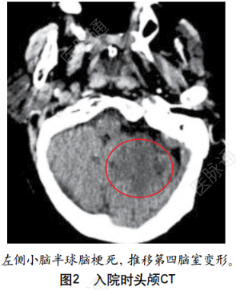

入院头颅CT示左侧小脑半球脑梗死(图2)。